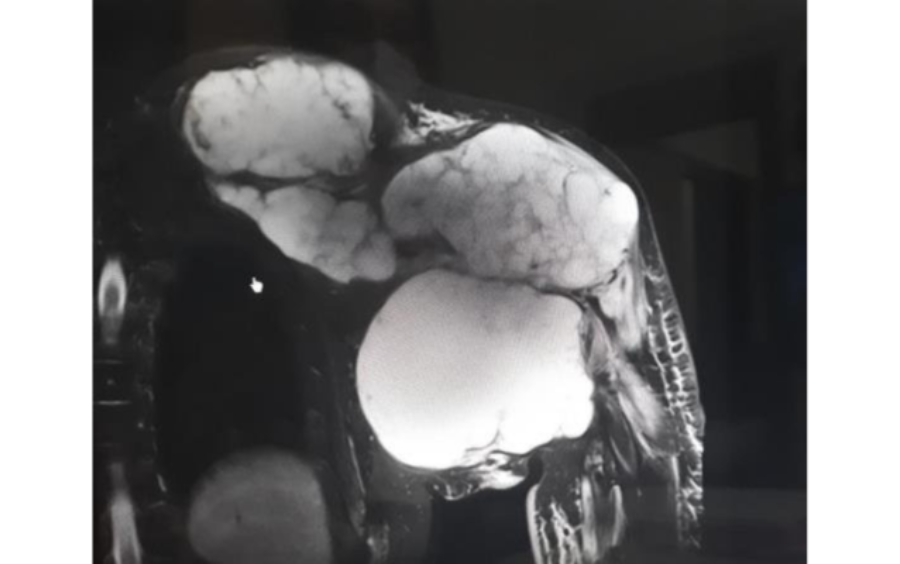

After histopathology, doctor diagnosed with Left side proximal humerus recurrent Chondrosarcoma.

Onco Orthopedic Dr. Pramod Chinder surgeon in Bangalore, decided the surgical plan- Considering the extensive extent and size of lesion, the surgery was divided into two parts performed on two different days: day 1 involved wide resection of the tumor in the left proximal humerus encasing the clavicle and scapula. Along with the tumor mass, upper half of scapula, lateral 2/3rd of clavicle and proximal half of the humerus had to be removed. Day 2- involved shoulder reconstruction with the help of 3D printed humerus, scapula, clavicle, and reverse shoulder arthroplasty implants. Incredible team discussed with Surgeon, the designing and entire manufacturing process. Read more